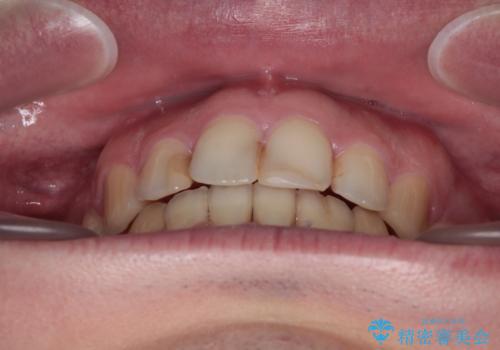

舌突出癖の改善トレーニングは、仕上がり、治療期間、そして治療後の後戻りに大きな影響を及ぼします。

トレーニングをしっかりと行っていただいたため、スッキリとした口元に仕上がりました。